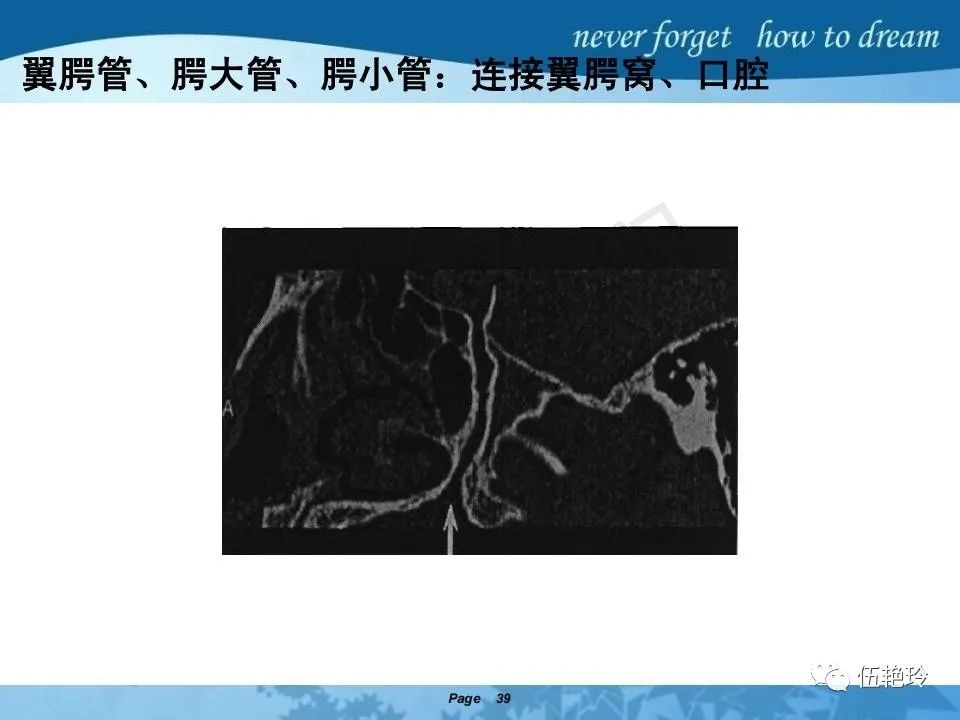

翼腭窝的解剖结构与鼻咽癌侵犯

2.31 向上颅内:①鼻咽顶壁→破裂孔(岩尖、斜坡)→蝶窦、海绵窦;②鼻咽顶壁→蝶骨基底部→蝶窦、海绵窦;③鼻咽侧壁→茎突前间隙→蝶骨大翼(卵圆孔)→海绵窦;④鼻咽侧壁→茎突前间隙→翼腭窝→ 颞下窝;⑤鼻咽前壁→鼻腔→翼突、翼腭窝→眶下裂→眶尖→海绵窦;⑥鼻咽前壁→鼻腔→上颌窦、筛窦;